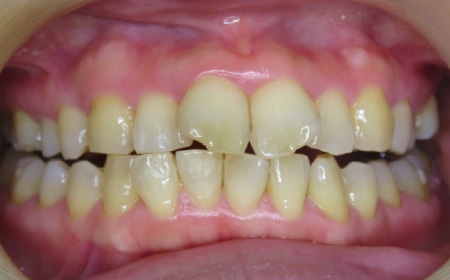

CASE01

Before

After